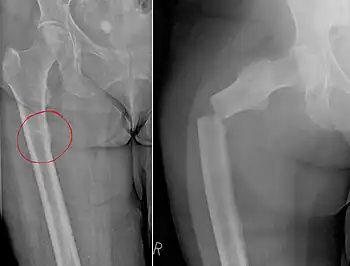

| Chalkstick fracture due to bone metastasis of breast cancer. Left image shows the metastasis, on the right a pathological fracture a few days later. | |

Chalkstick fractures are fractures, typically of long bones, in which the fracture is transverse to the long axis of the bone, like a broken stick of chalk.[1] A healthy long bone typically breaks like a hard woody stick as the collagen in the matrix adds remarkable flexibility to the mineral and the energy can run up and down the growth rings of bone. The bones of children will even follow a greenstick fracture pattern.